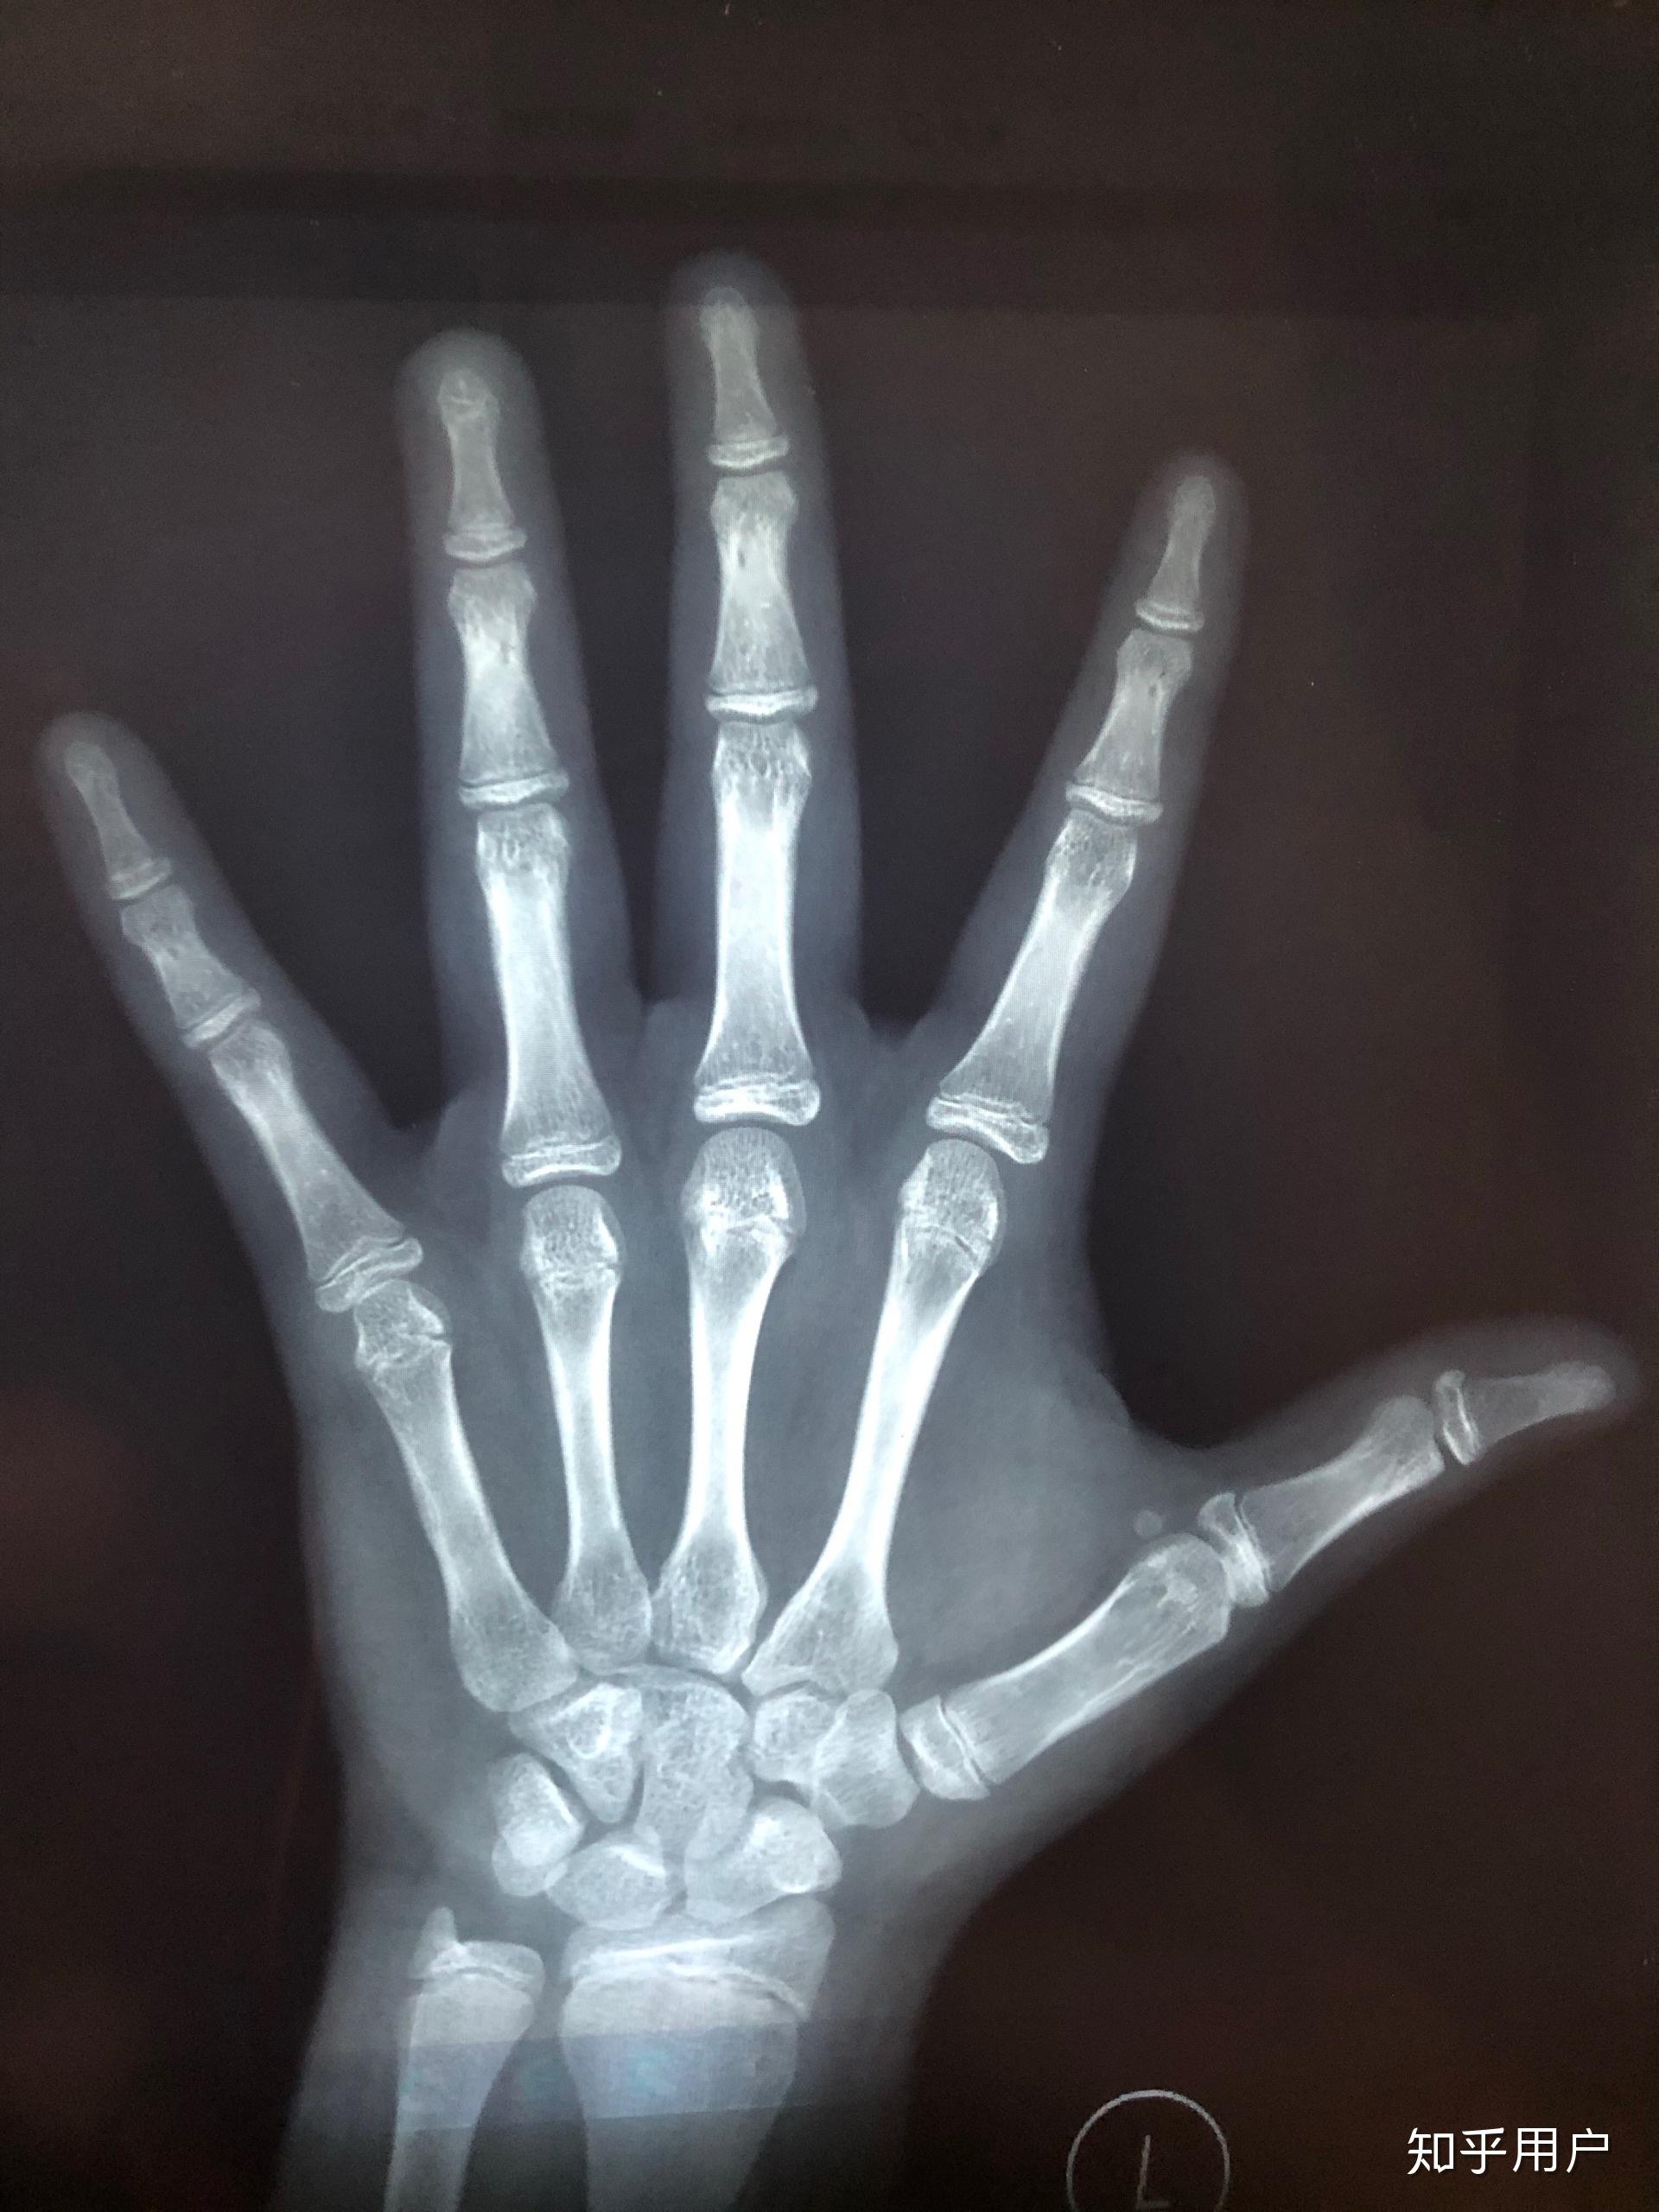

有懂的朋友能帮忙看看骨骼线闭合了吗? - 知乎

图片尺寸1920x2560